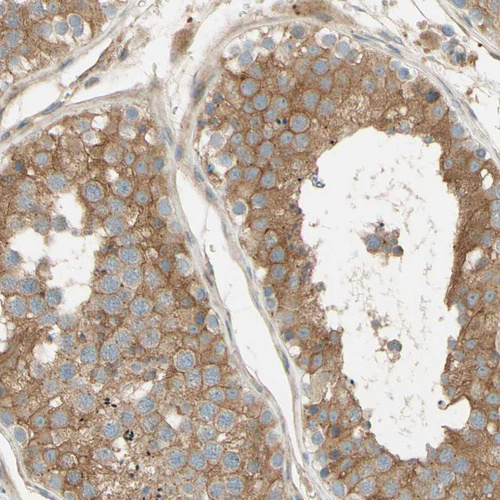

Immunohistochemical staining of human heart muscle shows moderate cytoplasmic positivity in cardiomyocytes.